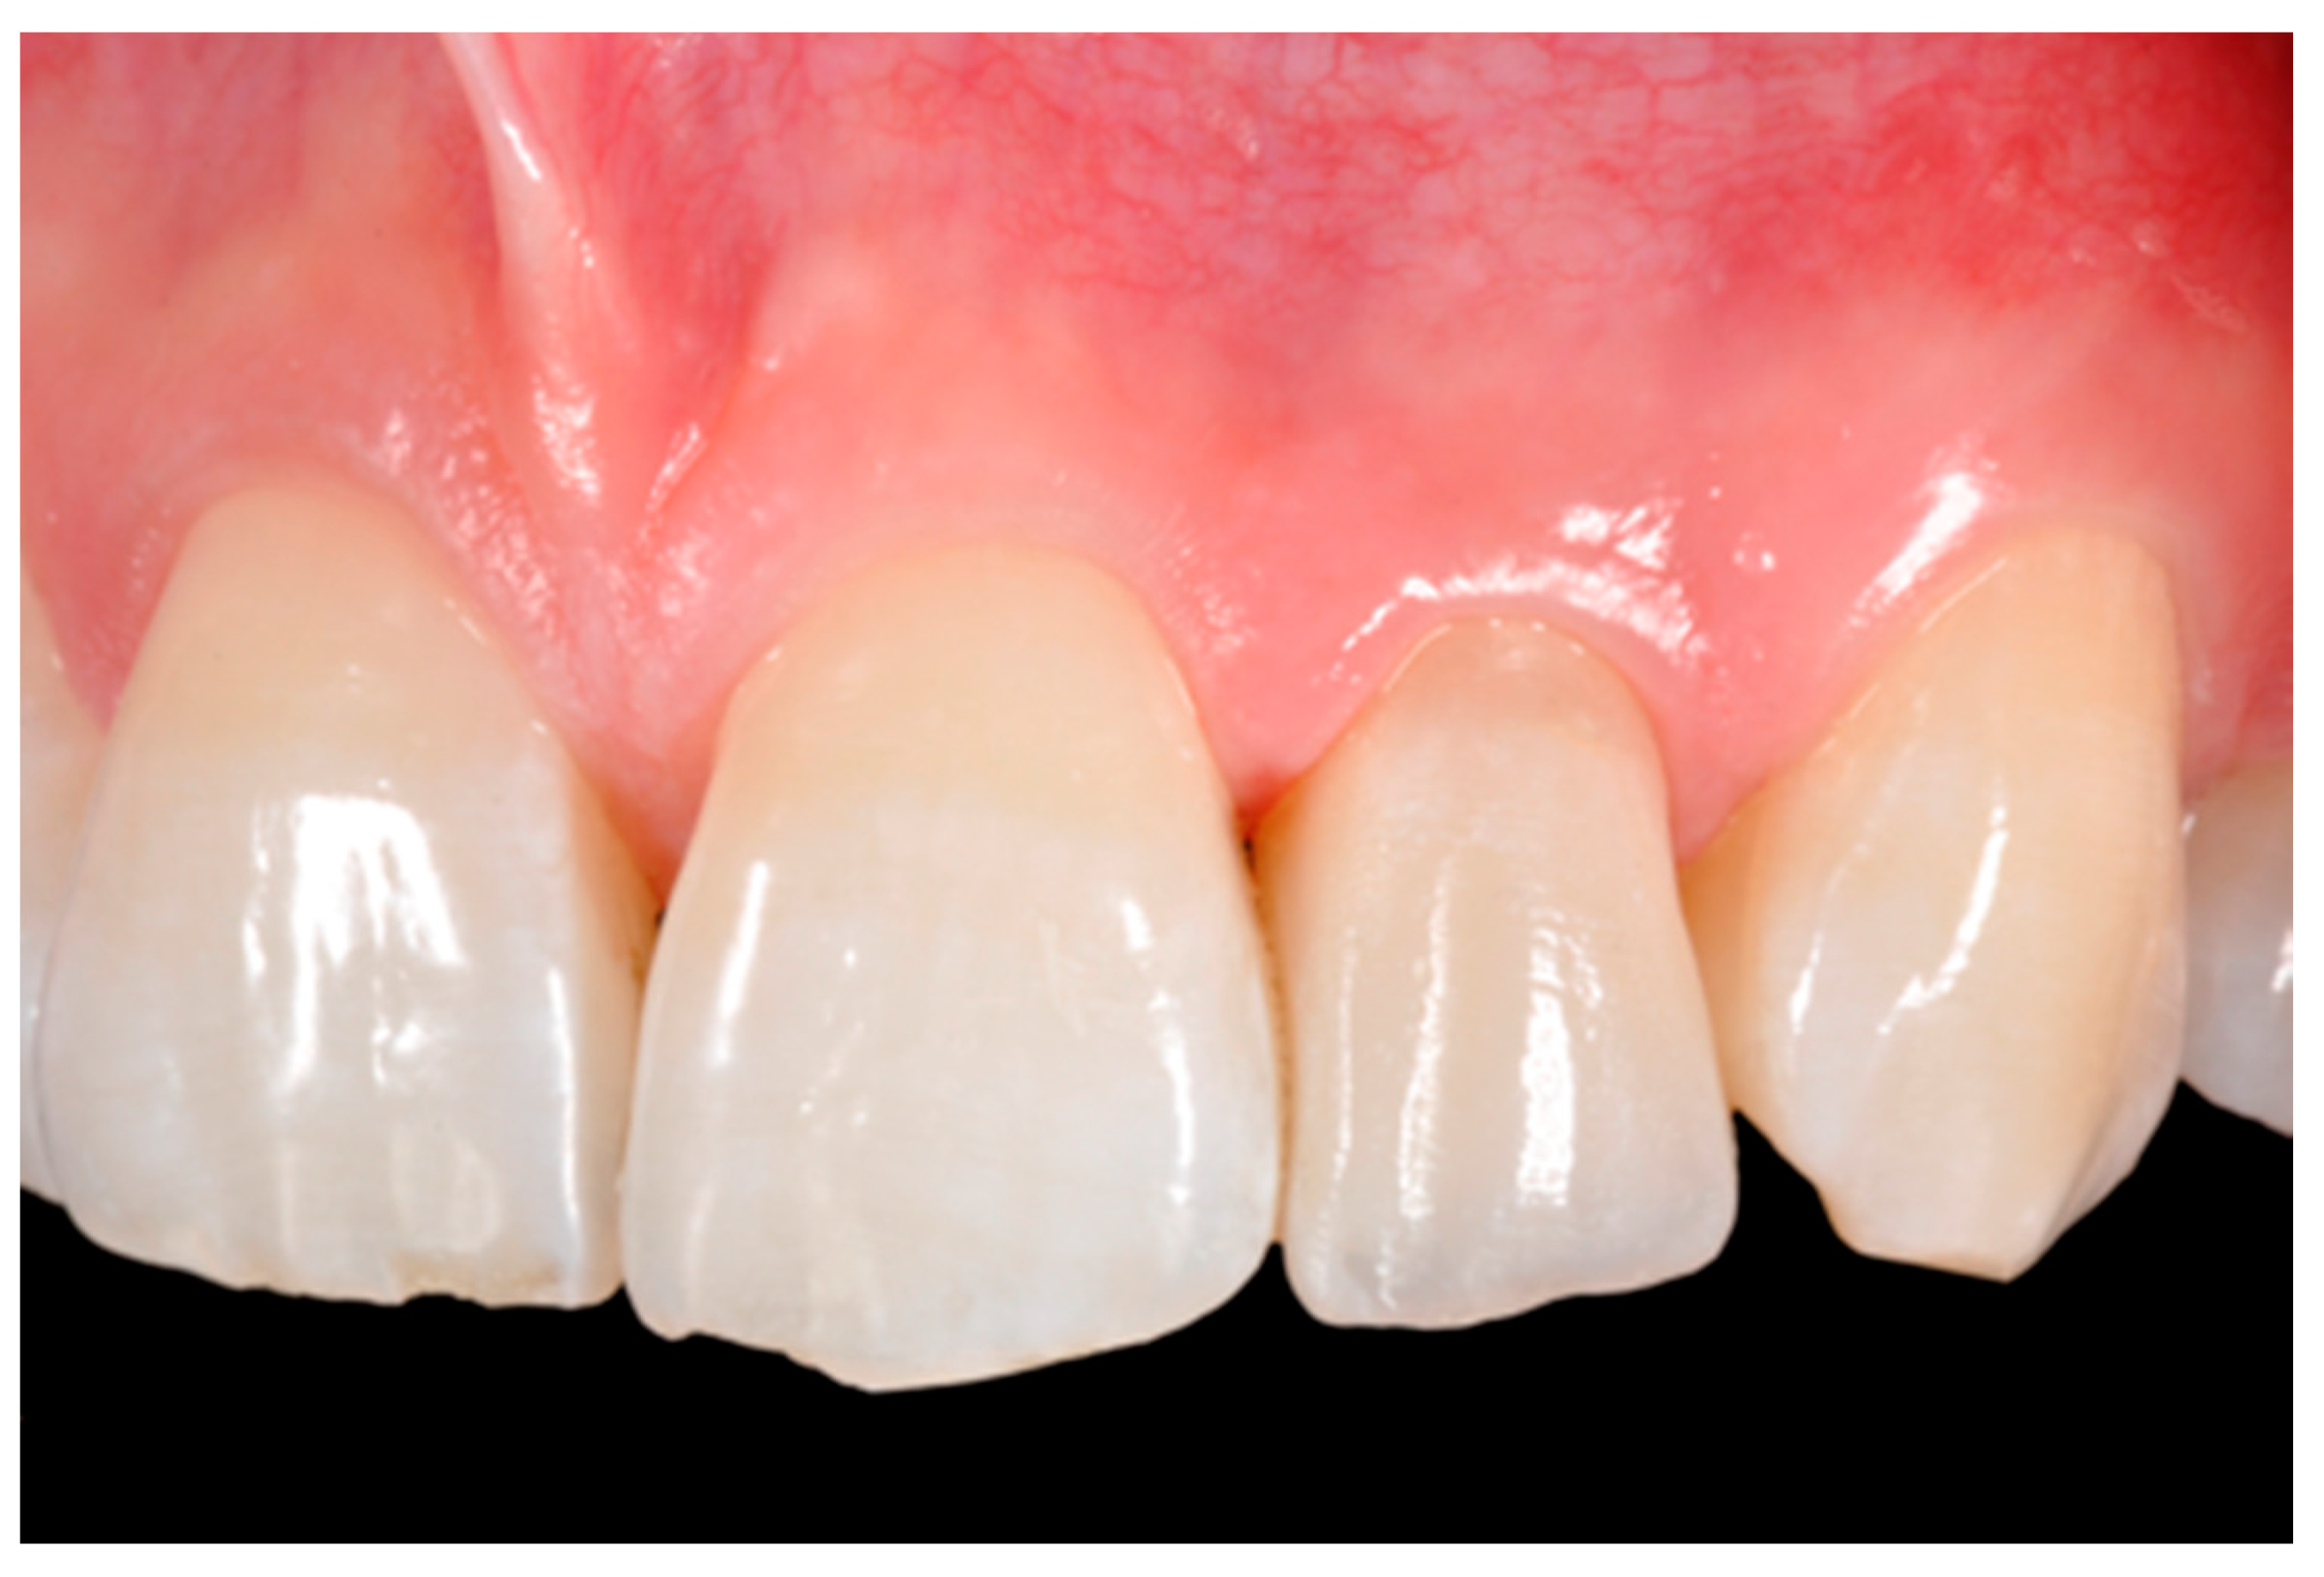

Finishing and polishing procedures were performed with a diamond bur (WL 268 014 Horico, Berlin, Germany), silicone points (Identoflex, Kerr, Bioggio, Switzerland) brushes (Jiffy Goat Air Brushes, Ultradent Products, South Jordan, UT, USA), and diamond pastes (Diamond Polish Mint, Ultradent Products, South Jordan, UT, USA) (Figure 13 and Figure 14). Satisfactory clinical and radiographic outcome was considered satisfactory at 3-months, 1-year, and 5-years post-operative (Figure 15, Figure 16, Figure 17, Figure 18 and Figure 19).

Figure 15.

Three months post-operative. Reprinted from Restauri diretti nei settori anteriori, G. Paolone, S. Scolavino, © 2021, with permission from Quintessence Publishing Italy.